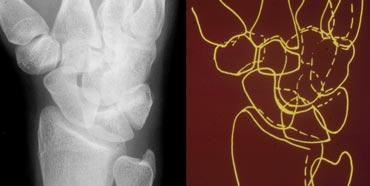

Quan sát các xương cổ tay như những mảnh ghép của trò chơi xếp hình — TRÁI: Hình minh họa sơ đồ cổ tay với các đường viền theo dõi bờ ngoài của các xương — PHẢI: Hình minh họa sơ đồ cổ tay với các đường theo dõi các xương cổ tay như những mảnh ghép xếp hình

Các khớp cổ tay cần có tính đối xứng. Hơn nữa, khi quan sát theo chiều tiếp tuyến (nhìn nghiêng), các bờ vỏ xương của các xương tạo nên khớp đó phải song song với nhau. Các bờ xương không được quan sát theo chiều tiếp tuyến sẽ không thể hiện tính song song này, ví dụ như phần xa của xương thuyền khớp với xương đầu.

Việc đánh giá tính song song này sẽ dễ dàng hơn khi xem các xương cổ tay như những mảnh ghép của trò chơi xếp hình khớp với nhau, thay vì theo dõi các xương cổ tay theo bờ vỏ xương ngoài tạo thành các đường viền (hình minh họa).

Khi một xương không song song với các xương còn lại, xương đó đã bị lệch khỏi vị trí. Nếu các xương còn lại vẫn song song với nhau, chúng vẫn giữ nguyên vị trí cùng nhau.

Hình ảnh bên trái cho thấy sự chồng lấp bất thường của xương nguyệt lên xương đầu, xương móc và xương tháp. Chúng ta cũng thấy bề mặt tiếp tuyến phía trong của xương thuyền, nhưng không có xương nào song song với nó. Ngoài ra còn có sự giãn rộng bất thường của khoang khớp quay-nguyệt. Các khớp còn lại vẫn song song và đối xứng tốt. Điều này dẫn đến kết luận rằng xương nguyệt đã bị di lệch trong khi các xương còn lại vẫn giữ nguyên vị trí cùng nhau.